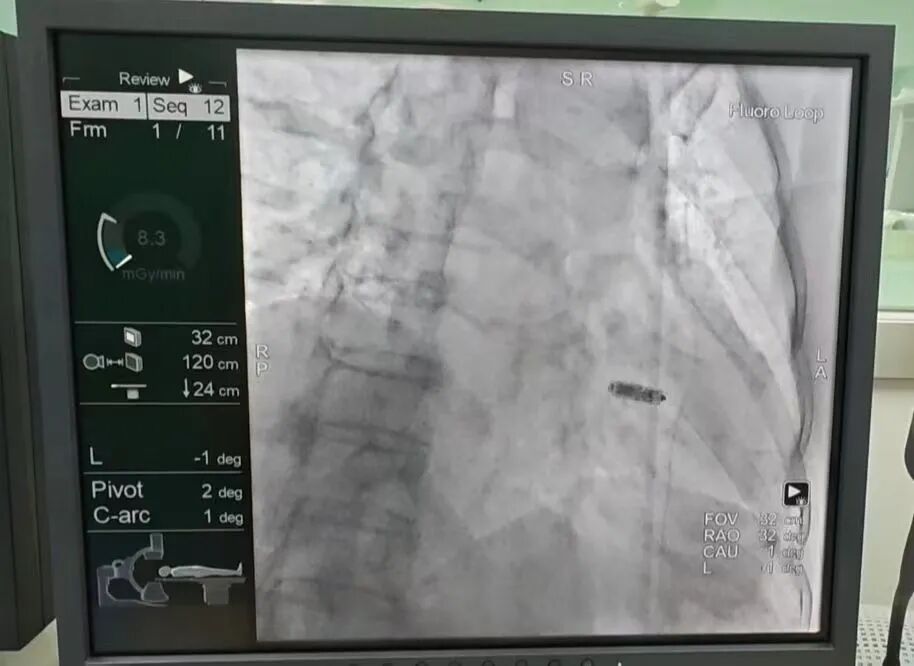

7、新疆医院介入诊疗中心启动运行

近日,心血管内科成功完成首例植入式心脏转复除颤器(ICD)植入手术,成功为一名III度房室传导阻滞的82岁高龄患者,实施首例无导线起搏器植入术(Micra AV型)。消化内科驻疆专家万晓龙教授成功开展首例内镜下逆行胰胆管造影(ERCP)胆总管取石术,标志着医院内镜诊疗水平迈上新台阶。

高难度介入诊疗技术的成功开展,标志着新疆医院介入诊疗中心进入快速发展轨道,助力国家区中高质量发展。